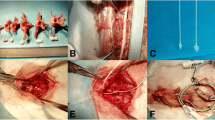

The spinal cord mechanical compression device comprised two parts: an in vivo IVCD and subcutaneous control module (SCCM) (Fig. 1; the size of the IVCD outer component was 8 × 11.3 × 24 mm and made of polyether ether ketone). The IVCD was equipped with a miniature reducer motor, metal push rod with a rubber head, transmitter lead, and spring. The head of the metal push rod was threaded, and a nylon compression head was screwed. The reducer motor was connected to the drive lead, which could maximally extend the push rod in the slide to 13 mm. The extrusion head radius was an umbrella with a radius of 2 mm and a thickness of 1.5 mm. The operating accuracy was 0.1 mm. The system self-locks when the motor stops. When the motor is reversed, the spring retracts the pushrod. The SCCM is composed of a control chip, Bluetooth module, and lithium battery controlled by a magnetic switch. The in vivo SCCM was fixed under the skin of sheep’s neck. The IVCD and in vivo SCCM were connected by a wire to receive the signal of the in vitro control system. The entire compression device was sealed with a silicon film with good biocompatibility. A stainless steel plate (316 L) with screws was used to fix the IVCD into the C2-3 intervertebral disk space.

Surgical placement of compression devices

After intravenous anesthesia, the sheep were placed in the supine position, and a right longitudinal incision was made through the anterior cervical approach to the front of the cervical vertebral body. Intraoperative radiographs confirmed the C2-3 intervertebral space. The intervertebral disk was removed to the posterior edge of the vertebral body. A curette and grinding drill were used to expand the space to the size of the compression device, and the compression device was fixed at the C2-3 intervertebral space with plates and screws. The initial position of the head of the pushrod was at the posterior edge of the vertebral body (Fig. 2), and SCCMs were implanted under the skin.